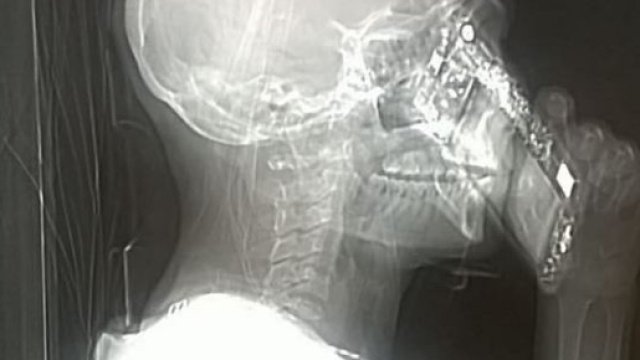

L'immagine che impazza sui social

Dimenticanza o dipendenza, il risultato è stato fantascientifico: la signora che nel corso della Tac ha risposto al telefono, ha dato vita ad un'immagine che sta impazzando sui social. Pare una cyber-donna, con un telefono che sta diventando parte di lei a tutti gli effetti. Anche se la signora si è giustificata dicendo di essere stata una dimenticanza.